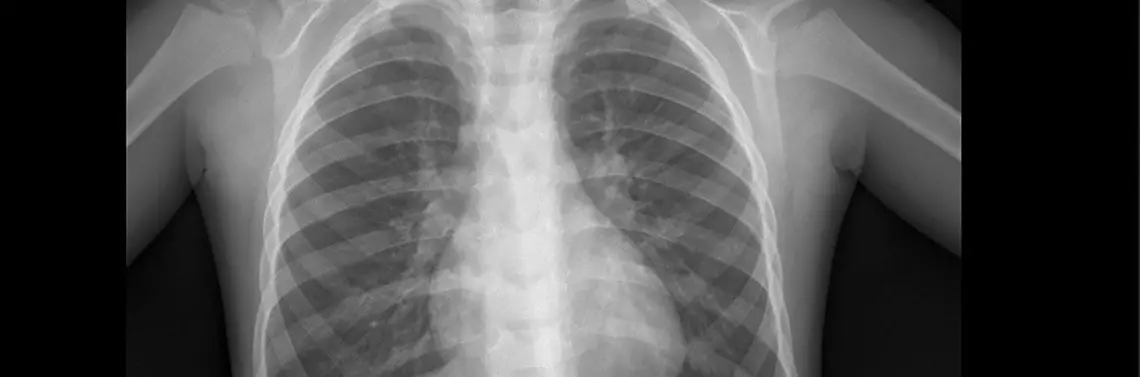

W wykonanych badaniach laboratoryjnych CRP 6,9 mg/l (norma < 5 mg/l), OB 24, pozostałe badania w tym morfologia, z rozmazem, jonogram, gazometria, mocznik, kreatynina prawidłowe. Test w kierunku obecności syncytialnego wirusa oddechowego (RSV) ujemny. Zdjęcie klatki piersiowej uwidoczniło zmiany zapalne (rycina 1).

Niewielkie pasmowate zagęszczenia odwnękowe w zakresie obu pól płucnych mogące odpowiadać zmianom zapalnym.

Poza tym pola płucne bez zagęszczeń ogniskowych. Kąty p-ż wolne.